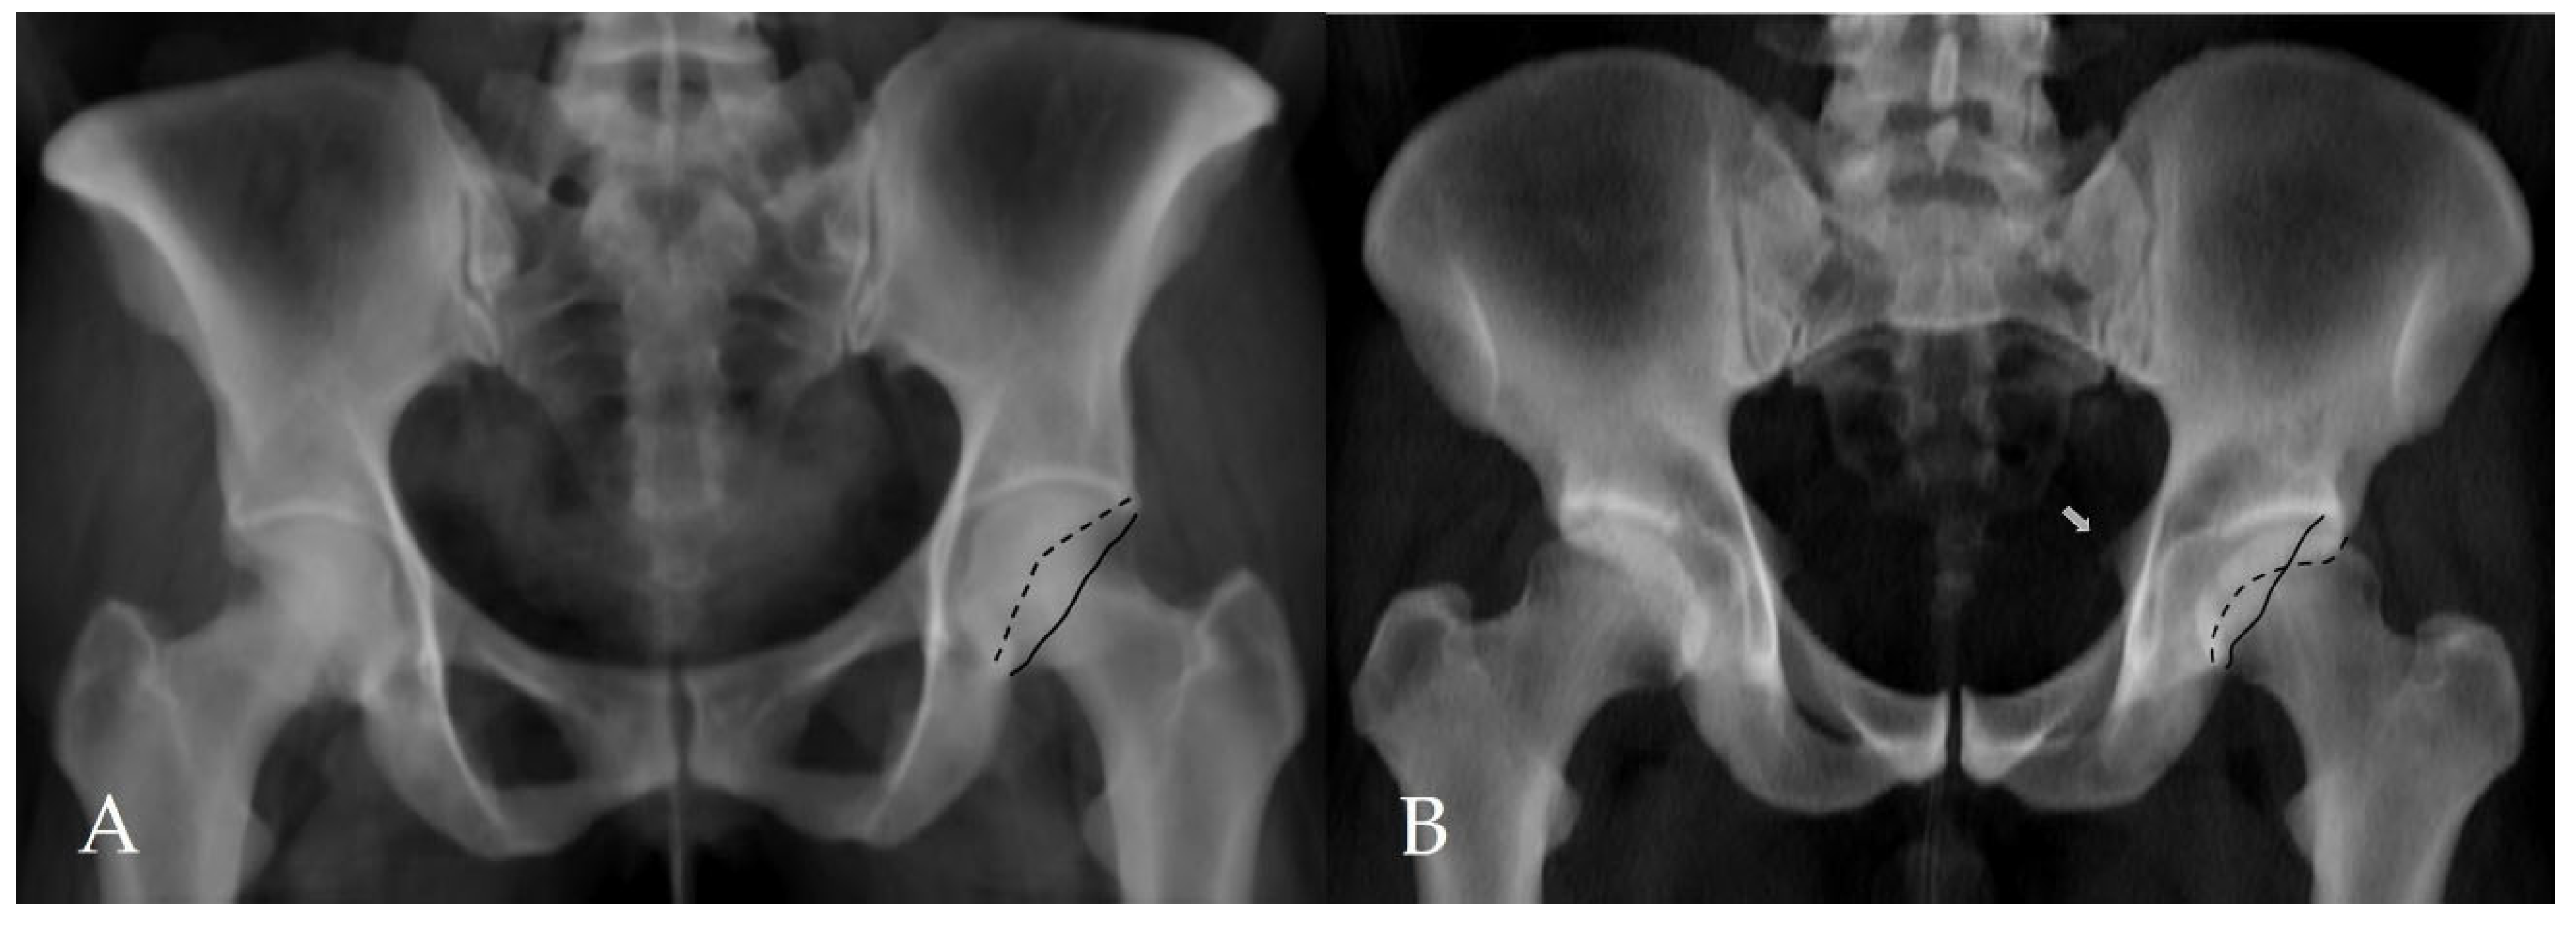

Figure 3.

Assessment of additional morphological parameters of femoroacetabular impingement on a CT-based virtual pelvic radiograph. (A) Negative acetabular crossover sign. The black solid line represents the posterior acetabular wall, and the black dashed line represents the anterior acetabular wall. (B) Positive acetabular crossover sign with an associated ischial spine sign (white arrow), suggestive of pincer-type femoroacetabular impingement and acetabular retroversion.